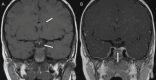

We report a 3-year-old male with findings of segmental agenesis of the corpus callosum, pituitary hypoplasia, and Chiari I malformation. The patient was born at 33 weeks and spent five weeks in the NICU for hypoglycemia, hypotension, and dyspnea. In infancy, the patient passed an adrenocorticotropic hormone stimulation test, while cortisol, growth hormone, and insulin-like growth factor levels were within reference range. Following height and weight percentile regression the patient underwent arginine and clonidine stimulation testing at 3 years of age, prompting pituitary evaluation via MRI. The results provided exemplary neuroimaging of segmental callosal agenesis, in which the genu and splenium form despite the absence of the callosal body. This finding adds support to a newer theory of embryological callosal development where progression does not occur linearly in the rosto-caudal direction.